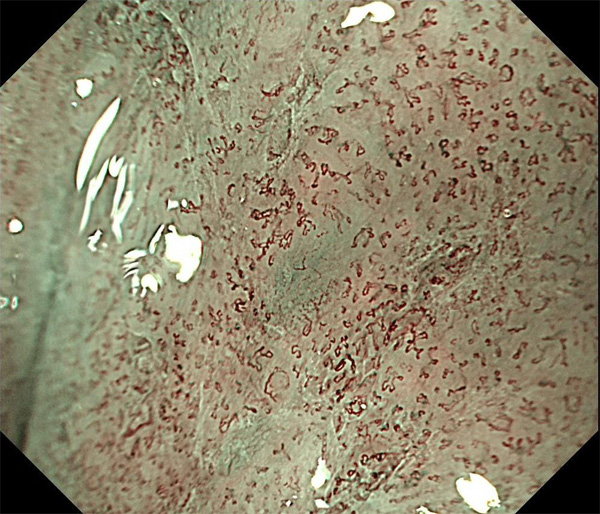

内視鏡所見と病理組織像の1対1対応が可能な症例を公募いたします。主にLSBEに発生した早期癌(HGDを含む)を対象としますが、興味深い症例であればSSBE癌でも結構です。採否は世話人へご一任ください。

症例呈示希望者は応募用紙に記入の上、代表的な内視鏡(2枚)、切除標本(新鮮、固定)、切り出し図、マッピング、代表的組織像とともに、Barrett 食道研究会事務局 barrett.shinshu@gmail.comへお申し込み下さい(10MB以下でお願い致します)。

特に、本邦では極めて稀なlong segment Barrett’s esophagus(LSBE)から発生した早期癌は、診断に難渋する場合も多く、欧米ではランダム生検による検出が標準的とされています。背景のBarrett食道もろとも全体を内視鏡切除+ラジオ波焼灼する欧米と異なり、ESDで内視鏡的な局所切除が基本の本邦では、存在診断+範囲診断(特に水平)を的確に行うことが不可欠です。

そのためには、一流の病理医による組織学的診断とエキスパート内視鏡医による拡大内視鏡像との一対一対応を徹底的に行うことで、『本来、見えないであろう拡大所見の先にある組織構築像が診えてくる』所まで内視鏡診断レベルを上げていく必要があります。その実現には、一対一対応を追究した症例(特にLSBE発生例)1例でも多く経験するしかありません。本研究会でBarrett食道腺癌(LSBE発生早期病変)を共に学び、拡大内視鏡像の一歩先を診るスキルを習得しましょう!一人でも多くの皆様のご参加をお待ちしています。